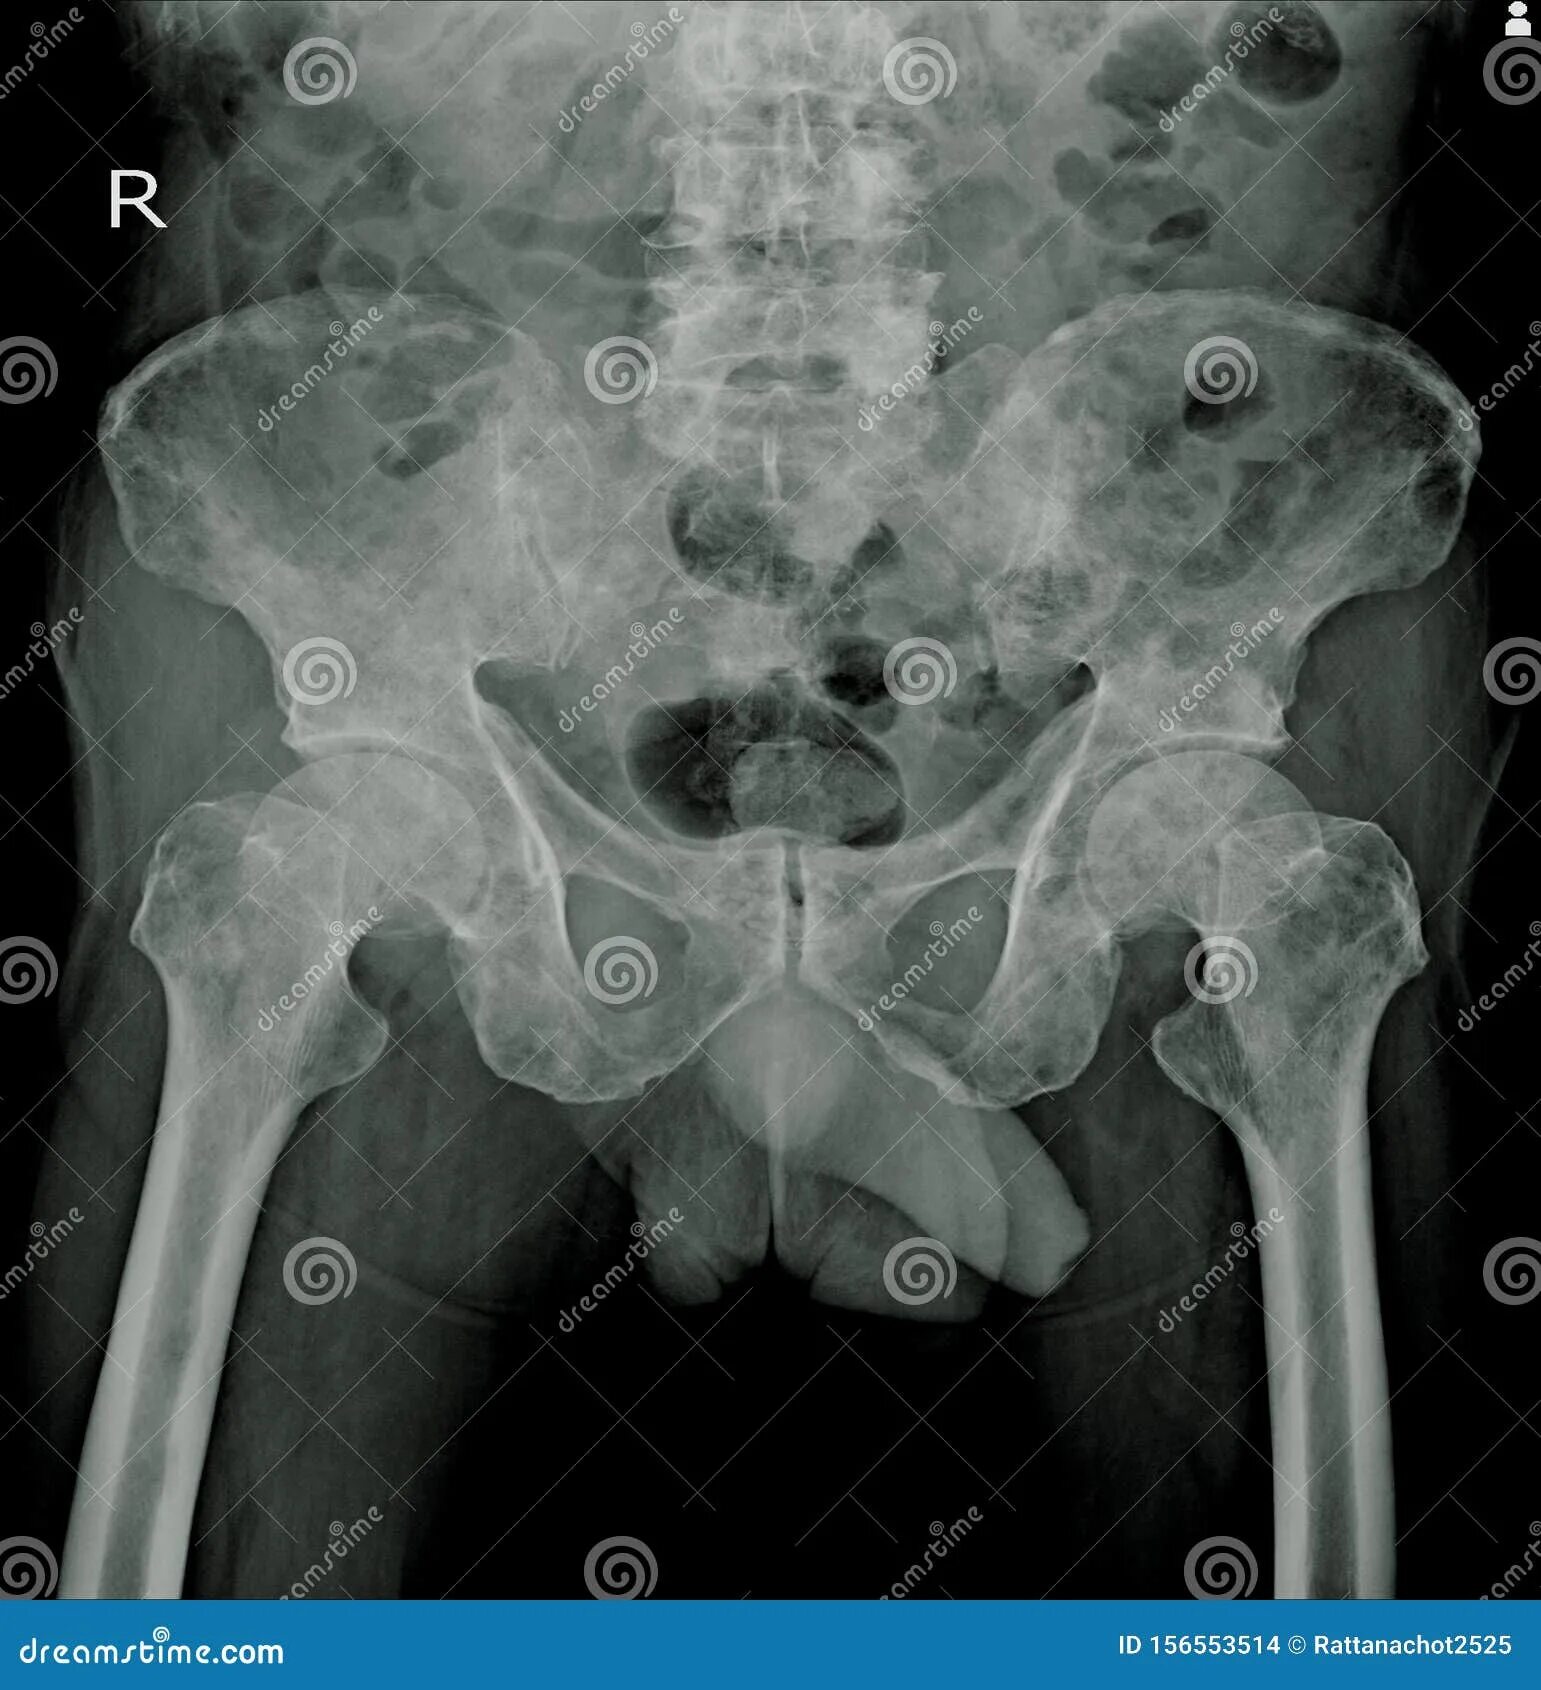

Метастазы в тазобедренном